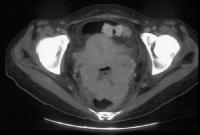

Stage Ib carcinoma confined to the cervix. CT image shows a mass with slightly heterogeneous area of attenuation expanding the cervix and surrounded by a thin rim of relatively preserved stroma. The cervical margins are smooth, well defined, and intact. Parametrial soft-tissue stranding or masses are lacking, and the periureteral fat planes are preserved. Cervix, cancer. CT image depicts a large lobulated mass replacing the cervix and showing non-uniform hypoattenuation. The air and fluid in the center of the mass are consistent with tumor necrosis and complicating infection (the patient had purulent discharge). The central hypoattenuation in the uterine corpus is suggestive of minimal fluid in the cavity.